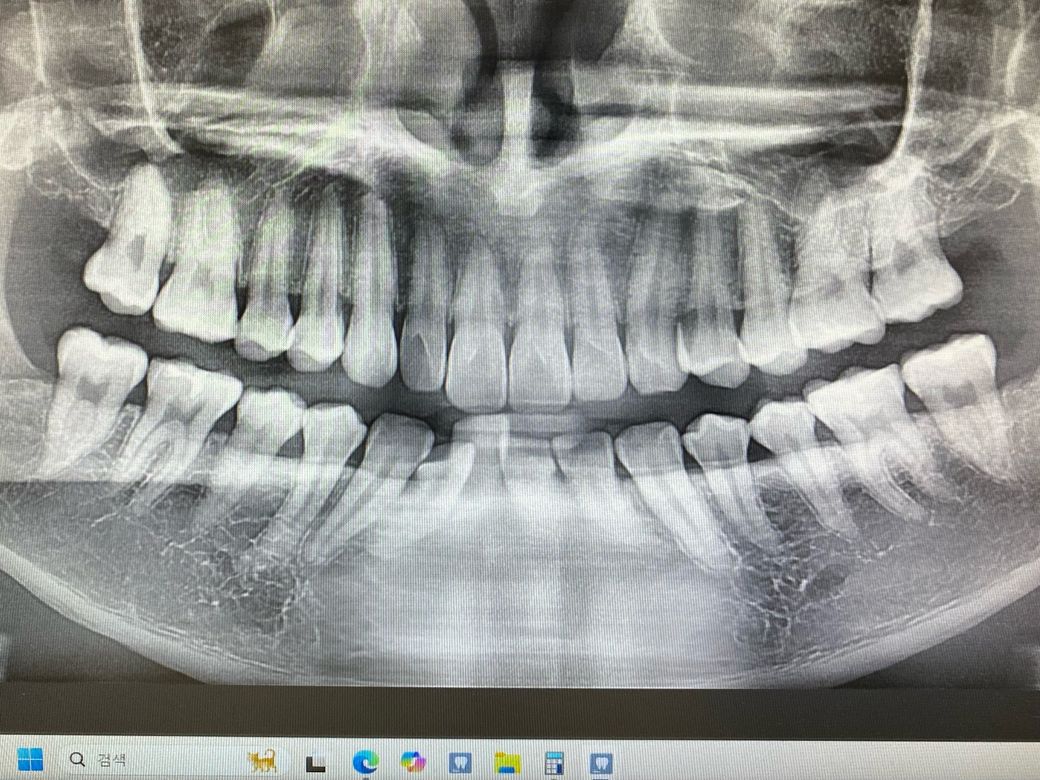

1치과는 충치가 있는 것 같다 양 옆 색상 차이가 있다 눈으로 확인 되는 정도라면 치료 해야 할 시기이다

위치 왼쪽 위 2번째 어금니 치료 한 부위 2차 충치

왼쪽 위 4번째와 3번째 사이 인접면 충치

2치과는 엑스레이로 찍어보고 육안으로 봐도

치료할 정도는 아니고 성인이니 검진 주기를 짧게 해서경과를 지켜보자

3치과는 엑스레이와 육안검사 확대 엑스레이 까지

찍었지만 너무 작다 자신들이 치료하는 기준에

미치지 못해서 치료하지 않고 경과를 지켜보자

• 3번 째 사진

사진에 보이는 정도면 충치가 안쪽에 많이 진행됫을 가능성이 있습니다. 저라면 인레이로 치료를 할것같습니다.

육안으로 보였을 경우 인절면에 충치가 있는 것으로 보입니다. 하지만 방사선상에는 크게 보이진 않습니다. 눈으로 보이는 충치가 있기 때문에 인접면 충치는 치료를 하는 것이 좋을 것으로 생각됩니다.

레진보다는 인레이를 하는 것이 일반적이며 레진은 술자를 잘 선택하셔야 합니다. 치료는 필요해보입니다.